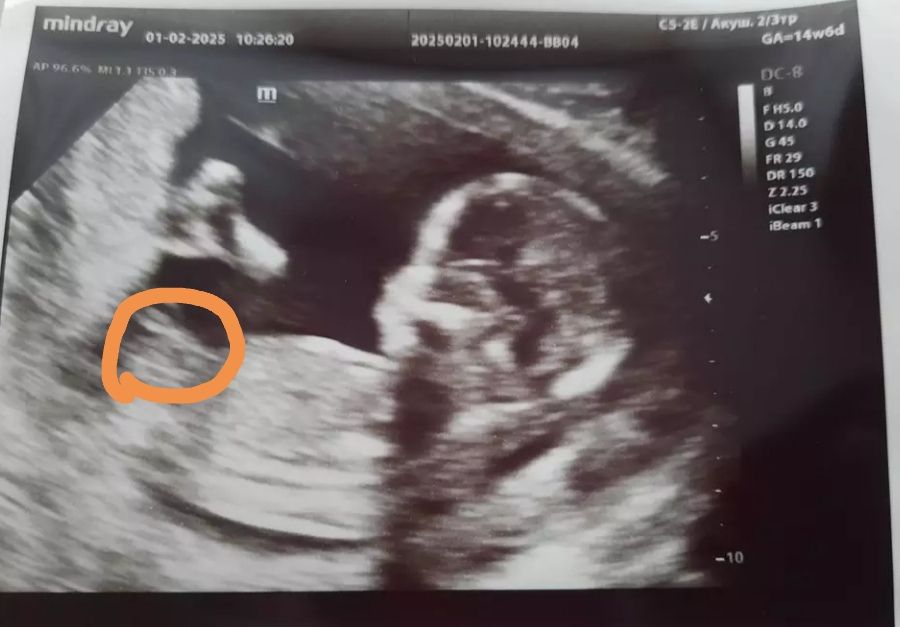

А точно мальчик?

Что-то ракурс на фото не очень понятен..

Конкретно на этом фото не видно.

Мальчик

Конечно мальчишка☺️, пимпа торчит.

Ирина Лапина, а где именно тут эта помпа?

На фото не очень понятно, половой бугорок не вижу, а так у меня с мальчиками ни когда не ошибались, если на первом узи сказали Он , значит так и было, а вот с девочками было сомнительно 🤷